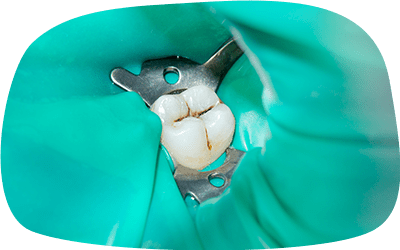

ラバーダム防湿の使用

治療中の感染を防ぐために、ラバーダム防湿を使用します。この技術により、根管内を清潔に保ち、細菌の侵入を防ぎます。